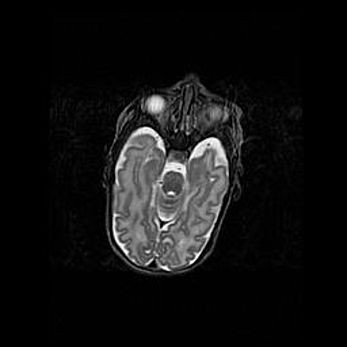

Неполная лизэнцефалия (пахигирия). Открытая гидроцефалия.

Возраст: 17 дней

Вес: 3110 г

Пол: мужской

Окружность головы: 33,5 см

Срок гестации: 35-36 недель

Лизэнцефалия—недоразвитие корковой пластинки и мозговых извилин в результате нарушения миграции нейронов коры. Поверхность мозговых полушарий гладкая. Микроскопически выявляется отсутствие нормальных слоев коры и скопление групп нейронов в подкорковом белом веществе.

Пахигирия—уменьшение числа вторичных извилин. В пораженном полушарии нервные клетки образуют толстый недифференцированный слой с неправильно расположенными нервными волокнами и группами гетеротопных клеток. Нервные клетки незрелые. Белое вещество истончено. При этом нередко аномально развит корково-спинномозговой путь.